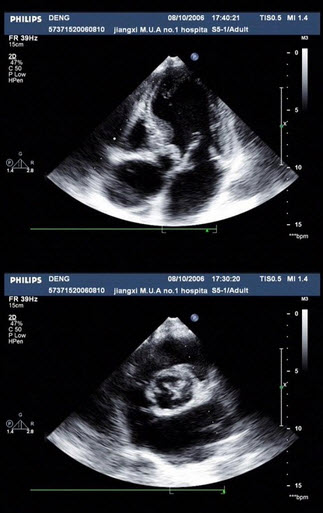

45、单项选择题

如图,初步超声诊断为()

A.二尖瓣返流

B.三尖瓣返流

C.主动脉瓣返流

D.肺动脉瓣返流

E.以上均不是